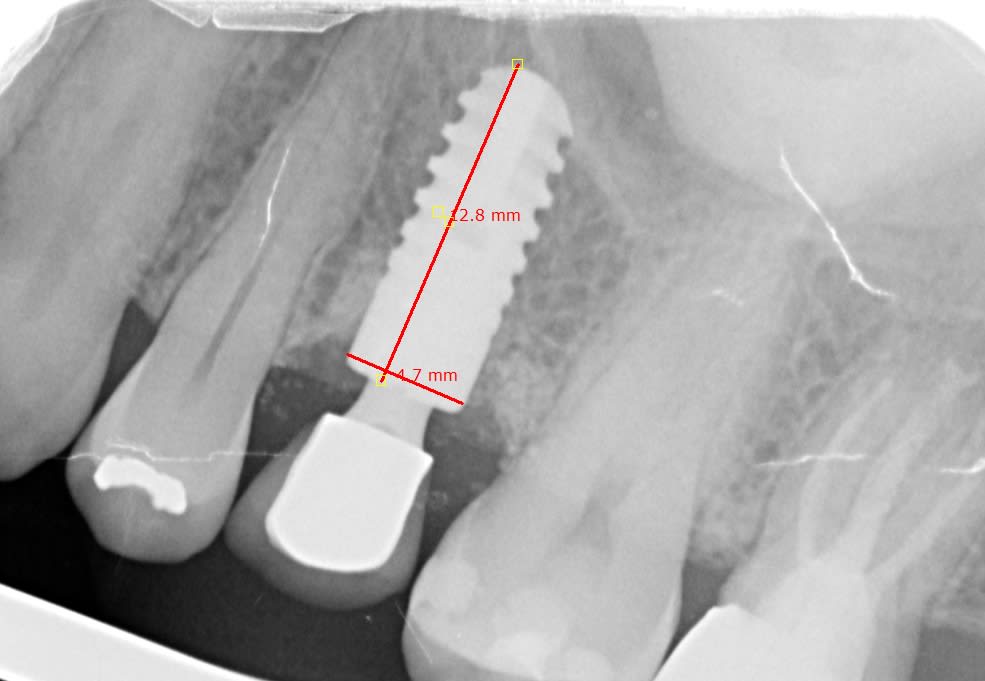

Quelqu'un reconnait-il cet inconnu, introuvable sur what's impalnt.

Posé en 2001 dans le 78.

Cône morse, Ça ressemble beaucoup à un Ankylos 1ère génération.